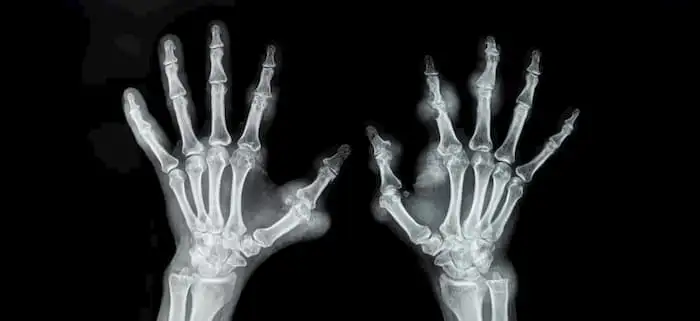

Вплив вибору дієти на ризик розвитку ревматоїдного артриту

Певні харчові звички, включаючи вживання алкоголю під час їжі, знежиреного молока та маргарину, пов'язані з підвищеним ризиком розвитку ревматоїдного артриту, тоді як включення в раціон спредів зі зниженим вмістом жиру може знизити цей ризик.

Таким чином, вживання алкоголю під час їжі, а також включення в раціон знежиреного молока і маргарину позитивно корелювало з розвитком РА, в той час як споживання знежирених спредів було пов'язане зі зниженням ризику розвитку цього захворювання. Враховуючи зростаючий інтерес до прецизійної медицини та персоналізованого догляду, розуміння взаємозв'язку між генетикою, харчуванням та ризиком захворювань має фундаментальне значення для розробки краще таргетованих втручань.